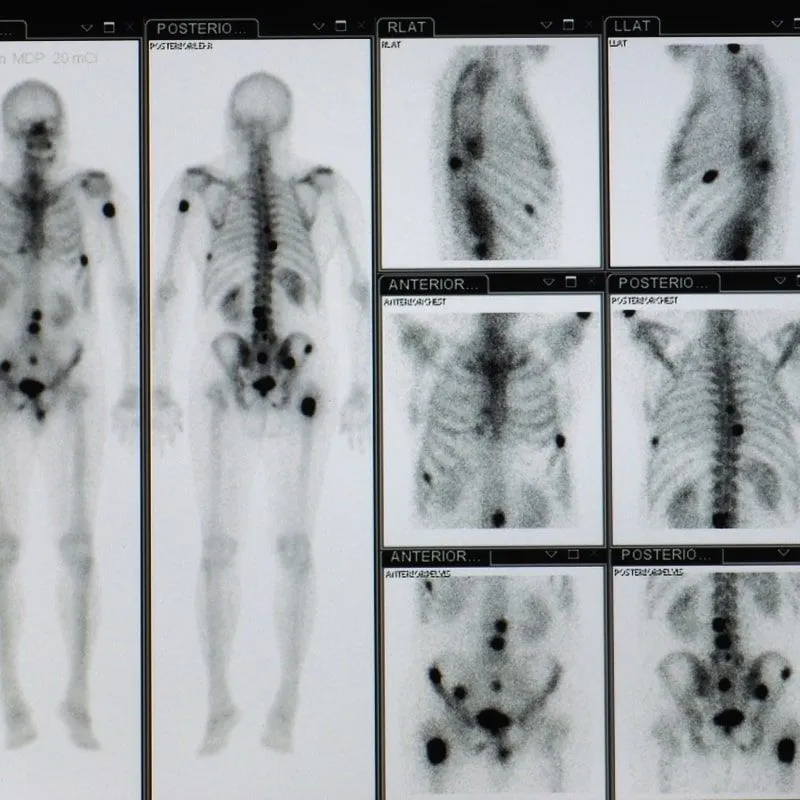

Dr. Ola Landgren shares about his innovative ImmunoPET technology and initial results.

C. Ola Landgren, MD, PhD, is Professor of Medicine, Chief of the Myeloma Program, and Leader of the Experimental Program at the University of Miami Sylvester Cancer Center. Read more about his move to Miami here. Dr. Landgren is a pioneer in the drug development and minimal residual disease (MRD) testing in myeloma. In collaboration with colleagues throughout the world, he develops new strategies (including cell-based, molecular-based, and imaging-based) and continues to be a leader of using advanced MRD testing in clinical trials. He is involved in the service’s rational treatment program (small molecule, monoclonal antibody, immune-based) for newly diagnosed, relapsed and refractory myeloma and amyloidosis patients. His research focuses on early drug development, advanced disease monitoring by new minimal residual disease (MRD) assays and biomarkers, and immune-PET to monitor treatment. He also studies mechanism and markers of progression from MGUS/smoldering myeloma to symptomatic multiple myeloma, and the identification of high-risk precursor patients who may be candidates for early treatment. Prior to joining Miami, Dr. Landgren was the Chief Attending Physician of the Myeloma Service at Memorial Sloan Kettering and Professor of Medicine at the Weill Cornell Medical College in New York City and Chief of the Multiple Myeloma Section of the National Cancer Institute in Bethesda, MD. Dr. Landgren received his MD at Karolinska Institute in Stockholm, Sweden; and he has had fellowships at Karolinska University Hospital and the National Cancer Institute. He is a frequent speaker at national and international meetings, and has published more than 400 peer-reviewed papers.